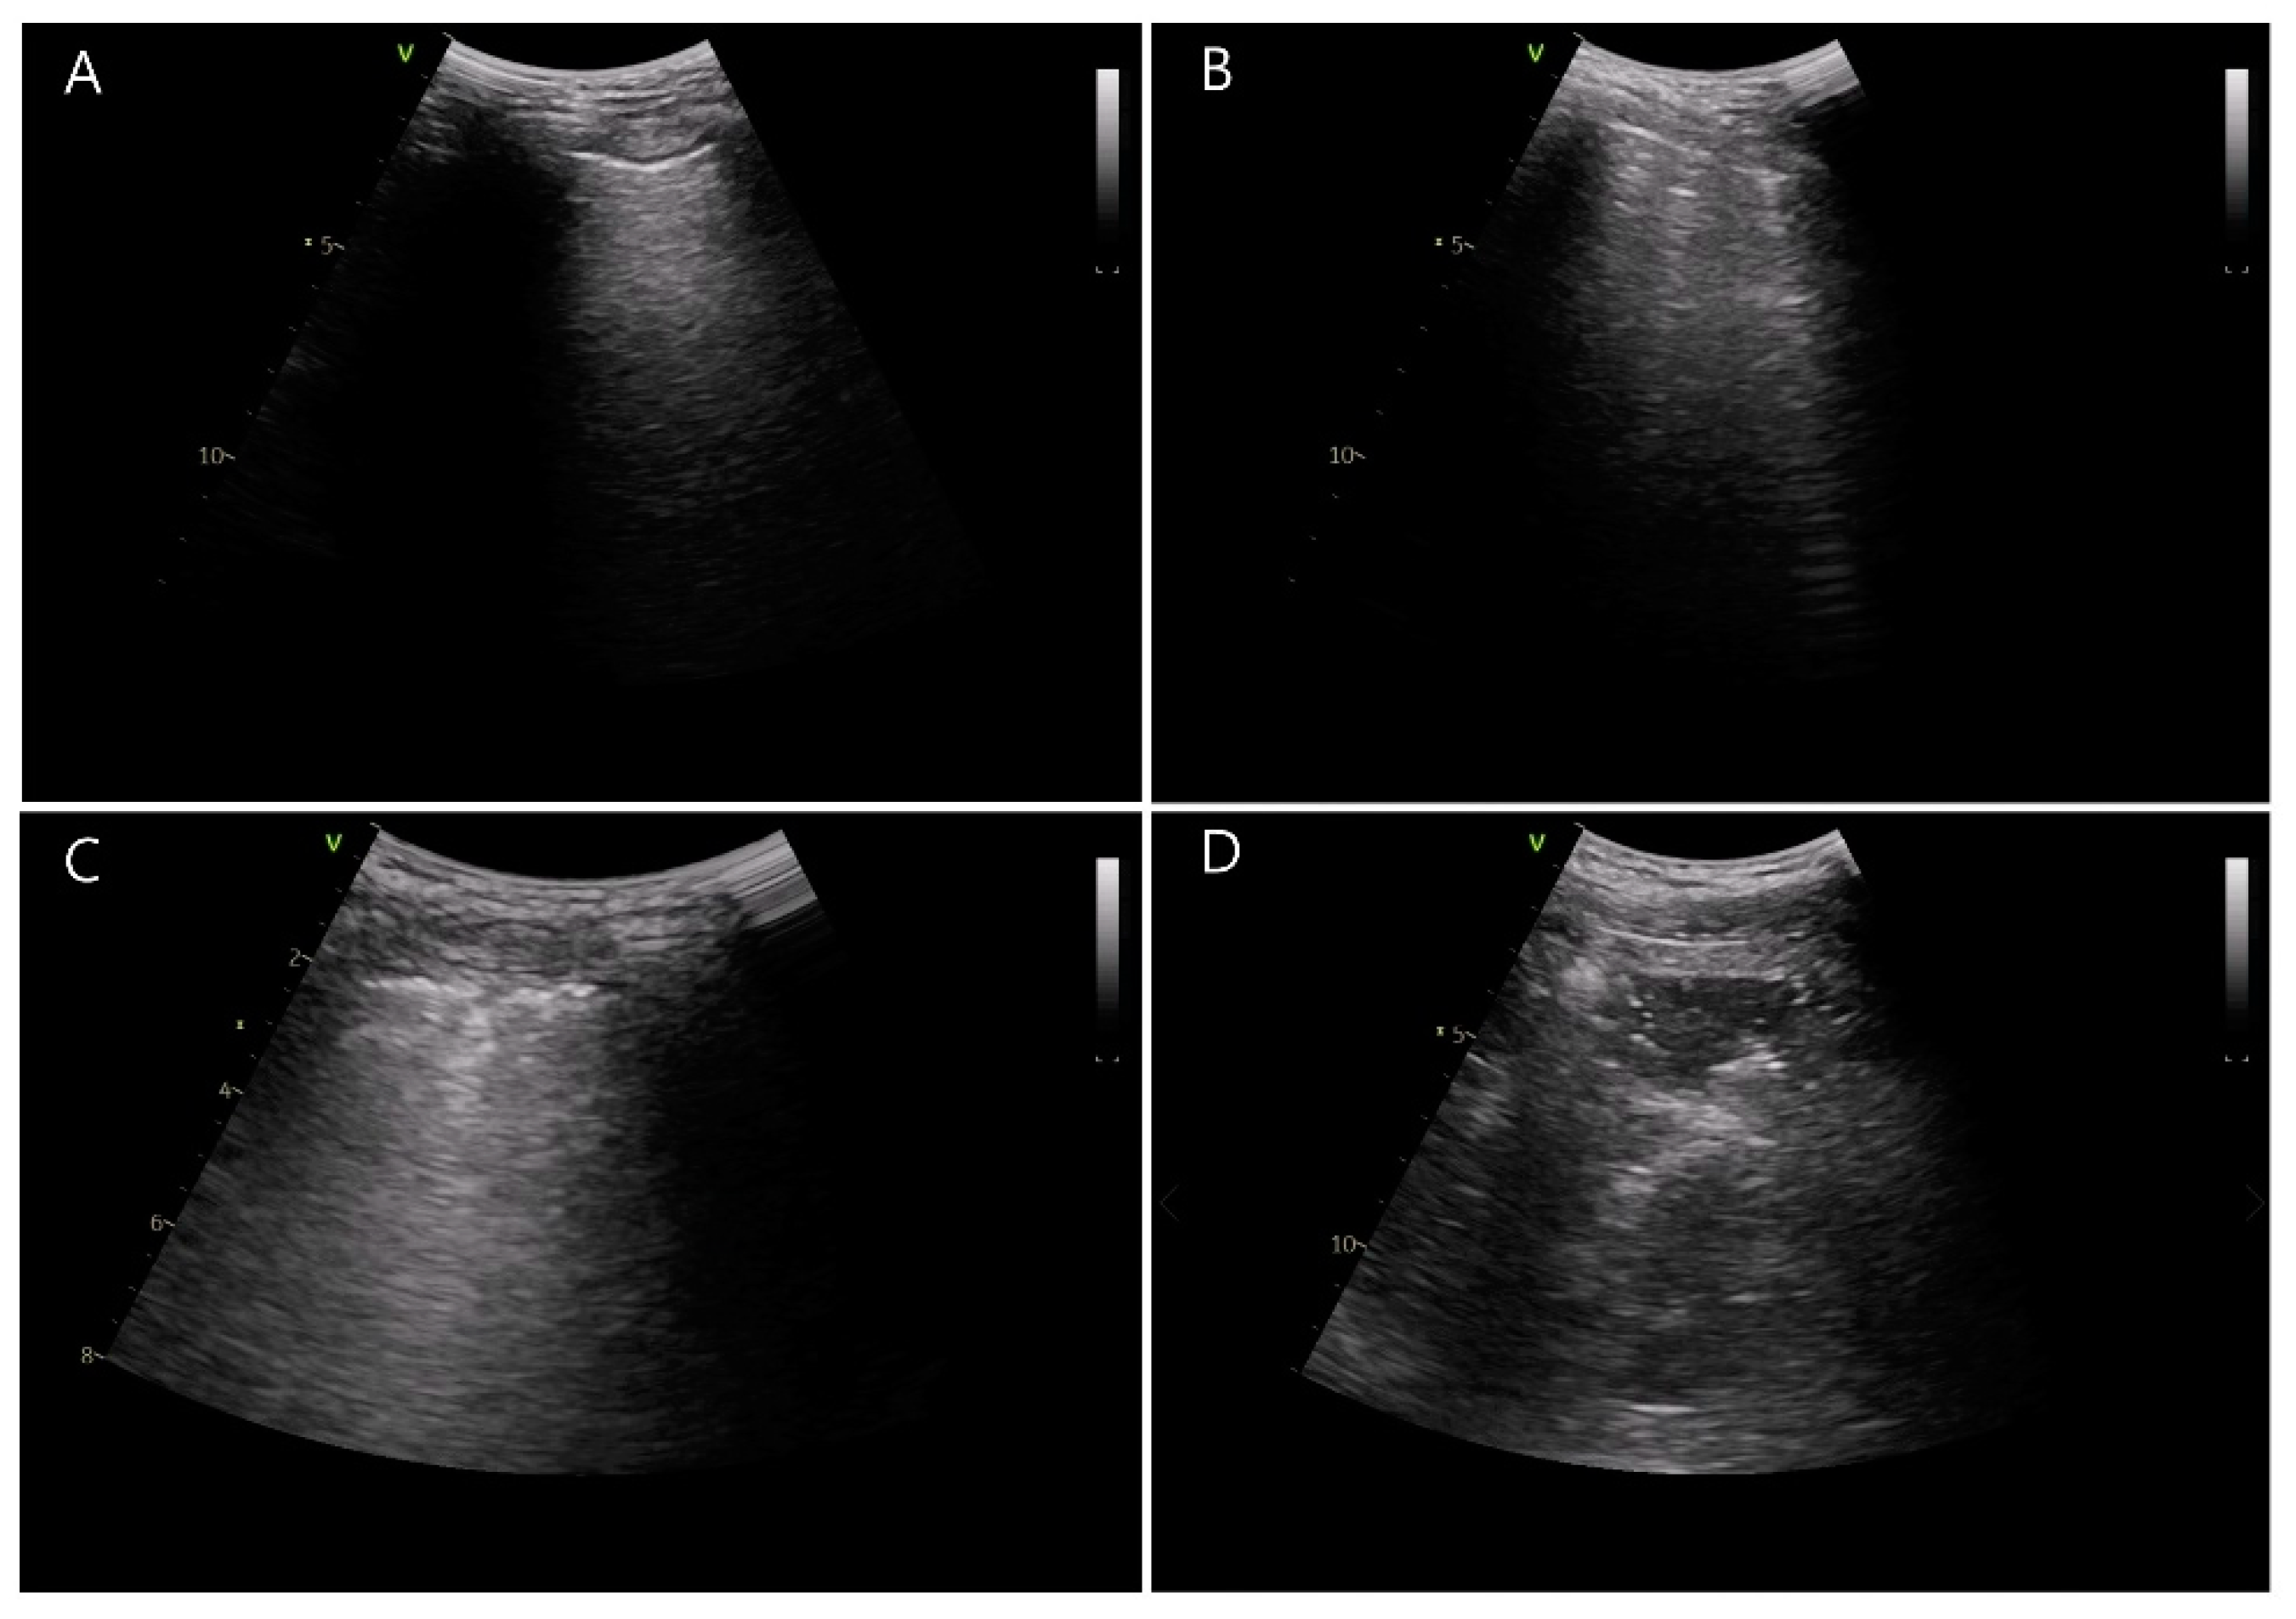

- Acosta, C.M.; Maidana, G.A.; Jacovitti, D.; Belaunzarán, A.; Cereceda, S.; Rae, E.; Molina, A.; Gonorazky, S.; Bohm, S.H.; Tusman, G. Accuracy of Transthoracic Lung Ultrasound for Diagnosing Anesthesia-induced Atelectasis in Children. Anesthesiology 2014, 120, 1370–1379. [Google Scholar] [CrossRef] [PubMed]

- Monastesse, A.; Girard, F.; Massicotte, N.; Chartrand-Lefebvre, C.; Girard, M. Lung Ultrasonography for the Assessment of Perioperative Atelectasis. Anesth. Analg. 2017, 124, 494–504. [Google Scholar] [CrossRef] [PubMed]

- Volpicelli, G.; International Liaison Committee on Lung Ultrasound (ILC-LUS) for the International Consensus Conference on Lung Ultrasound (ICC-LUS); Elbarbary, M.; Blaivas, M.; Lichtenstein, D.A.; Mathis, G.; Kirkpatrick, A.W.; Melniker, L.; Gargani, L.; Noble, V.E.; et al. International evidence-based recommendations for point-of-care lung ultrasound. Intensive Care Med. 2012, 38, 577–591. [Google Scholar] [CrossRef]